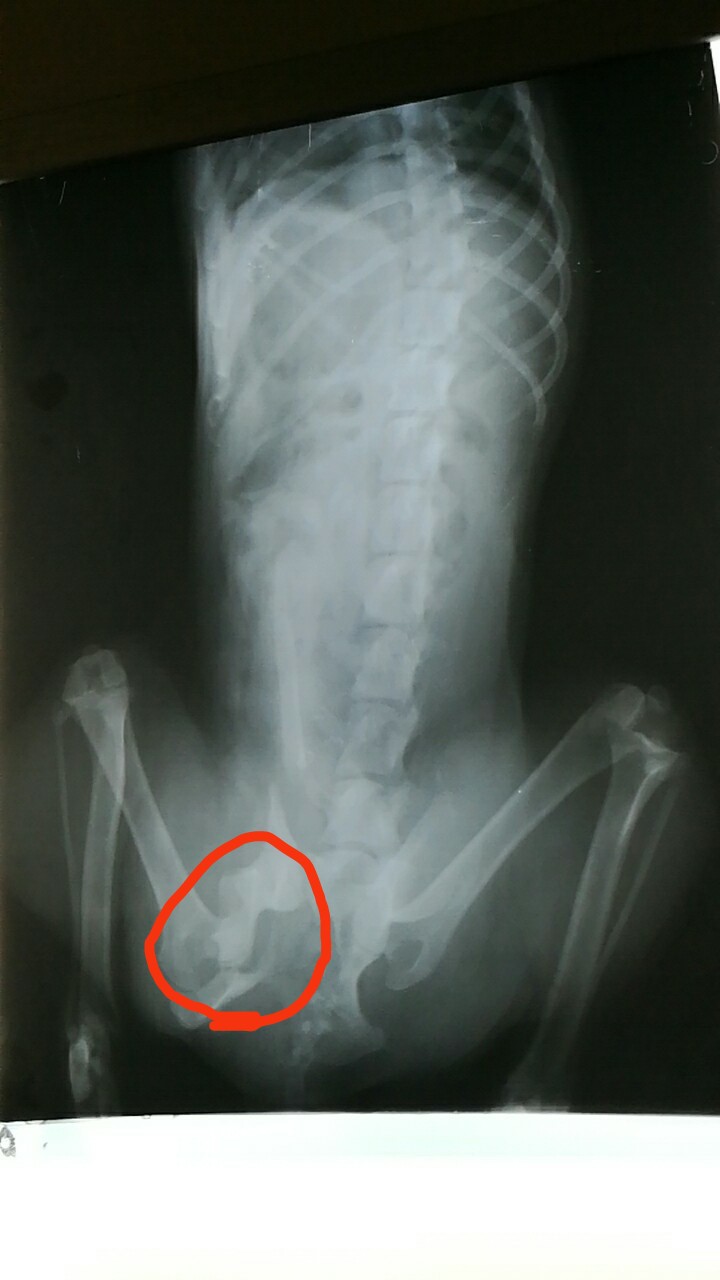

由于沒(méi)做絕育手術(shù),歡歡見(jiàn)到馬路對(duì)面有母狗在吸引,不顧一切掙脫主人的韁繩,跑向馬路對(duì)面只聽(tīng)“哐”一聲被車撞到,緊急聯(lián)系我院,經(jīng)檢查左髖骨骨折。所以對(duì)于不以繁殖為目的狗狗要適齡絕育,避免因?yàn)榘l(fā)情期引起的車禍。